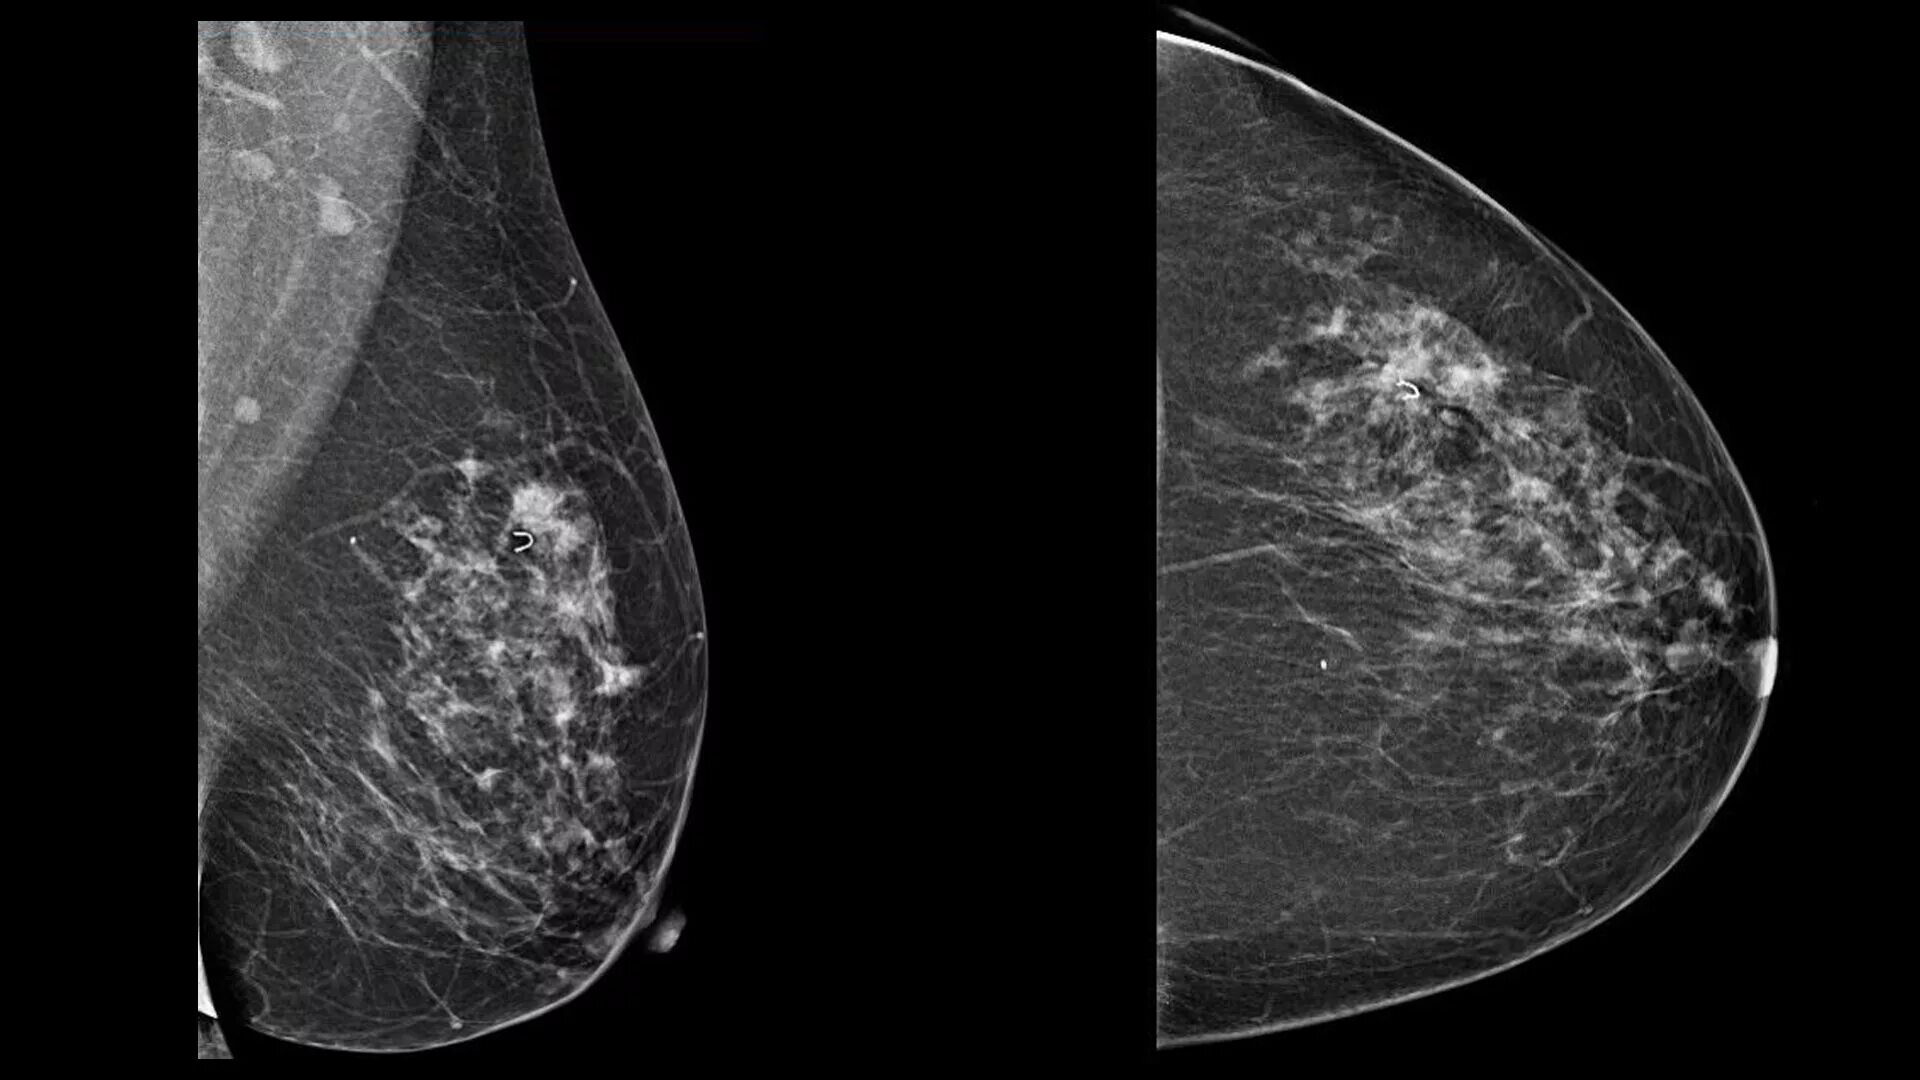

Новообразование в головном мозге. Презентация опухоль мозга. Опухоли головного мозга презентация. Злокачественная фиброаденома молочной железы. Фиброаденома молочной железы Размеры для операции. Фиброаденома молочной железы маммография. Листовидная опухоль гистология.

Злокачественная фиброаденома молочной железы. Фиброаденома молочной железы Размеры для операции. Фиброаденома молочной железы маммография. Листовидная опухоль гистология. Доброкачественная опухоль. Доброкачественныеопкхоли. Клетки, образующие доброкачественную опухоль:. Строение доброкачественной опухоли.

Петрокливальная менингиома. Менингиома доброкачественная. Злокачественные заболевания молочных желез. Новообразование молочной железы. Злокачественная опухоль молочной железы. Доброкачественные новообразования молочной железы.

Злокачественные заболевания молочных желез. Новообразование молочной железы. Злокачественная опухоль молочной железы. Доброкачественные новообразования молочной железы. Очаговые симптомы опухоли затылочной доли. Клинические проявления опухоли лобной доли:. Опухоль мозга височной доли симптомы. Опухоль затылочной доли головного мозга.

Гепатомегалия. Симптомы гепатомегалии. Умеренное увеличение печени. Умеренная гепатомегалия. Маммография косая проекция укладка. Маммография молочных желез. Маммография это исследование. Рентгеновская маммография.

Маммография косая проекция укладка. Маммография молочных желез. Маммография это исследование. Рентгеновская маммография. Подчелюстная слюнная железа на рентгене. Сиалография слюнных желез. Рентгенография слюнных желез. Контрастная сиалография слюнных желез.

Глиобластома мультиформная степень 4. Неоперабельная глиобластома головного мозга.. Глиобластома лобной доли мрт. Глиобластома злокачественная опухоль агрессивная. Филлоидная фиброаденома молочной железы УЗИ. УЗИ признаки доброкачественных опухолей молочных желез. Доброкачественная опухоль молочной железы на УЗИ. Опухоль молочной железы на УЗИ.

Филлоидная фиброаденома молочной железы УЗИ. УЗИ признаки доброкачественных опухолей молочных желез. Доброкачественная опухоль молочной железы на УЗИ. Опухоль молочной железы на УЗИ. Хирургическая операция. Эндоскопическая операция. Хирургическое вмешательство. Эндоскоп хирургический.

Магнитно-резонансная томография легких. Магниторезонансная томография легких. Магнитно ядерная томография. Ядерно-магнитно-резонансная томография. Саркома молочной железы на маммографии. Фибросаркома маммография. Саркома молочной железы рентген. Болезнь Педжета молочной железы маммография.

Саркома молочной железы на маммографии. Фибросаркома маммография. Саркома молочной железы рентген. Болезнь Педжета молочной железы маммография. Типы роста опухолей. Инфильтративный Тип роста. Инфильтрирующий рост опухоли.

Опухоли задней черепной ямки. Объемное образование задней черепной ямки. Опухоли задней черепной ямки клиника. Канцер молочной железы. Онкология грудной железы. Онкологические заболевания груди. Опухоль молочной железы.

Канцер молочной железы. Онкология грудной железы. Онкологические заболевания груди. Опухоль молочной железы. Рентгеновские методы обследования. Рентгенологические методы исследования. Методики рентгенологического исследования. Методика рентген исследования.

Рентгеновские методы обследования. Рентгенологические методы исследования. Методики рентгенологического исследования. Методика рентген исследования. Очаговое образование молочной железы фиброаденома. Фиброзно-жировая инволюция молочных желез что это такое. Объемное образование в молочной железе. Злокачественные образования молочной железы.

Очаговое образование молочной железы фиброаденома. Фиброзно-жировая инволюция молочных желез что это такое. Объемное образование в молочной железе. Злокачественные образования молочной железы. Фиброламеллярная карцинома печени мрт. Фиброламеллярная карцинома печени кт. Доброкачественная опухоль печени мрт. Гепатоцеллюлярная карцинома мрт.

Опухоль печени доброкачественная кт. Первичные злокачественные опухоли печени. Злокачественные новообразования печени кт. Первичные и Метастатические опухоли печени. Маммография. Маммограмма молочных желез. Маммография после 40 лет проводится.

Маммография. Маммограмма молочных желез. Маммография после 40 лет проводится. Виды роста злокачественных опухолей. Рост злокачественных новообразований. Злокачественные опухоли характеризуются. Форма злокачественной опухоли.

Метастатическое поражение печени. Метастатические опухоли печени. Злокачественные образования печени. Молочная железа маммография. Мастопатия на маммографии. Опухоль молочной железы маммограмма. Рик молочной железы маммографич.

Молочная железа маммография. Мастопатия на маммографии. Опухоль молочной железы маммограмма. Рик молочной железы маммографич. Опухоль головного мозга симптомы. Новообразование в головном мозге. Раковые заболевания головного мозга. Объемное образование головного мозга.

Терминальная стадия онкологии. Опухоль грудной стенки кт. Опухоль в терминальной стадии. Маммография молочных желез объемное образование. Опухоль молочной железы. Онкология молочной железы. Опухольмолочныйжелезы.

Маммография молочных желез объемное образование. Опухоль молочной железы. Онкология молочной железы. Опухольмолочныйжелезы. Доброкачественная злокачественная опухоль головного мозга мрт. Глиома головного мозга мрт. Опухоль головного мозга на кт.